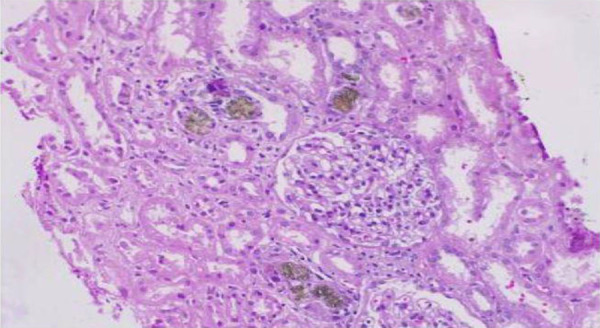

腺嘌呤磷酸核糖基转移酶(APRT)缺乏症是一种罕见的常染色体疾病,具有非常不同的表现。疾病范围从完全无症状到2,8-二羟基腺嘌呤(DHA)结石到大量沉积DHA晶体导致DHA结晶肾病。我们报告一例45岁的妇女谁提出了急性肾损伤和反复呕吐。肾活检显示急性肾小管损伤肾小管腔内棕色结晶沉淀,偏振光双折射特征,证实了DHA结晶肾病的意外诊断。她开始服用黄嘌呤氧化酶抑制剂,结果肾功能有所改善。本病例强调了一个事实,即APRT缺乏可以有多种表现,并且是结晶性肾病的重要遗传原因。

Adenine phosphoribosyltransferase (APRT) deficiency is a rare autosomal disorder with extremely variable presentation. The disease spectrum ranges from completely asymptomatic to 2,8-dihydroxyadenine (DHA) stones to massive deposition of DHA crystals leading to DHA crystalline nephropathy. We report a case of a 45-year-old woman who presented with acute kidney injury and recurrent vomiting. Kidney biopsy revealed precipitation of brown crystals in tubular lumina with acute tubular injury with characteristic birefringence on polarizing light, confirming the unexpected diagnosis of DHA crystalline nephropathy. She was started on a xanthine oxidase inhibitor which resulted in an improvement of kidney function. This case highlights the fact that APRT deficiency can have varied presentations and is an important hereditary cause of crystalline nephropathy.